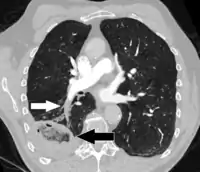

A Hampton hump in a person with a right lower lobe pulmonary embolism